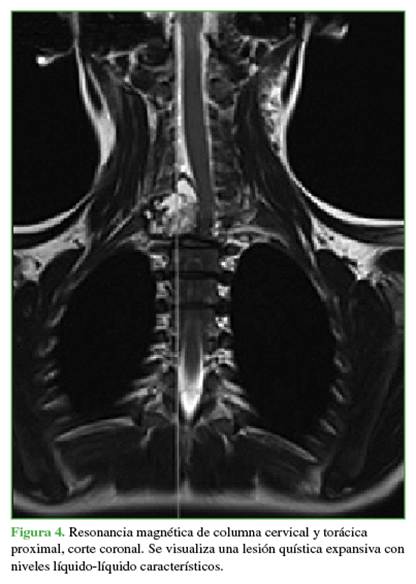

Los estudios complementarios mostraron un compromiso vertebral extenso: en C7 (arco posterior), zonas 4-7 y niveles III y IV de la clasificación de Weinstein-Boriani-Biagini; en T1 (cuerpo vertebral), zonas 10-3 y niveles III y IV; en T2 (pedículo derecho más arco posterior), zonas 3-7, niveles III y IV.11 Las lesiones eran de tipo quística expansiva (Figuras 3 y 4). Ante el patrón expansivo de la lesión, se descartó la sospecha de un hemangioma vertebral. Se interpretó el caso como una lesión con diagnóstico presuntivo de QOA grado 3 de Enneking.

Las radiografías, la tomografía computarizada y la resonancia magnética son los estudios complementarios que ayudan a llegar al diagnóstico. En las radiografías, se observa una cavidad expansiva osteolítica. En la tomografía y la resonancia, se visualizan los característicos niveles líquido/líquido.8